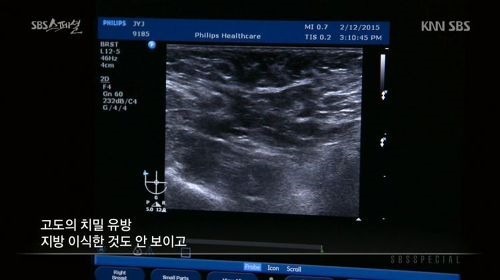

장윤주는 과거 SBS 교양프로그램 'SBS 스페셜-장윤주의 가슴 이야기'에서

"14살부터 가슴이 나오기 시작했다"며 "생각보다 크게 자랐다. 사이즈는 70에 C컵 정도 된다"고 털어놨다.

당시 방송에서 장윤주는 가슴을 초음파로 진단했습니다.

장윤주의 가슴 초음파 사진을 살펴본 의사는

"유선 조직이 가슴의 80%이상을 차지하고 있는 고도의 치밀유방이다. 지방 이식한 것도 안보인다. 보면 다 안다. (인공적인 것이)아무것도 없다. 자연산 맞다. 모유 잘 나오겠다"고 진단했습니다.

이에 장윤주는 "저의 가슴 수술논란을 확실히 풀었다"며 기뻐하며 "저도 꼭 모유수유하고 싶다"고 말했습니다.